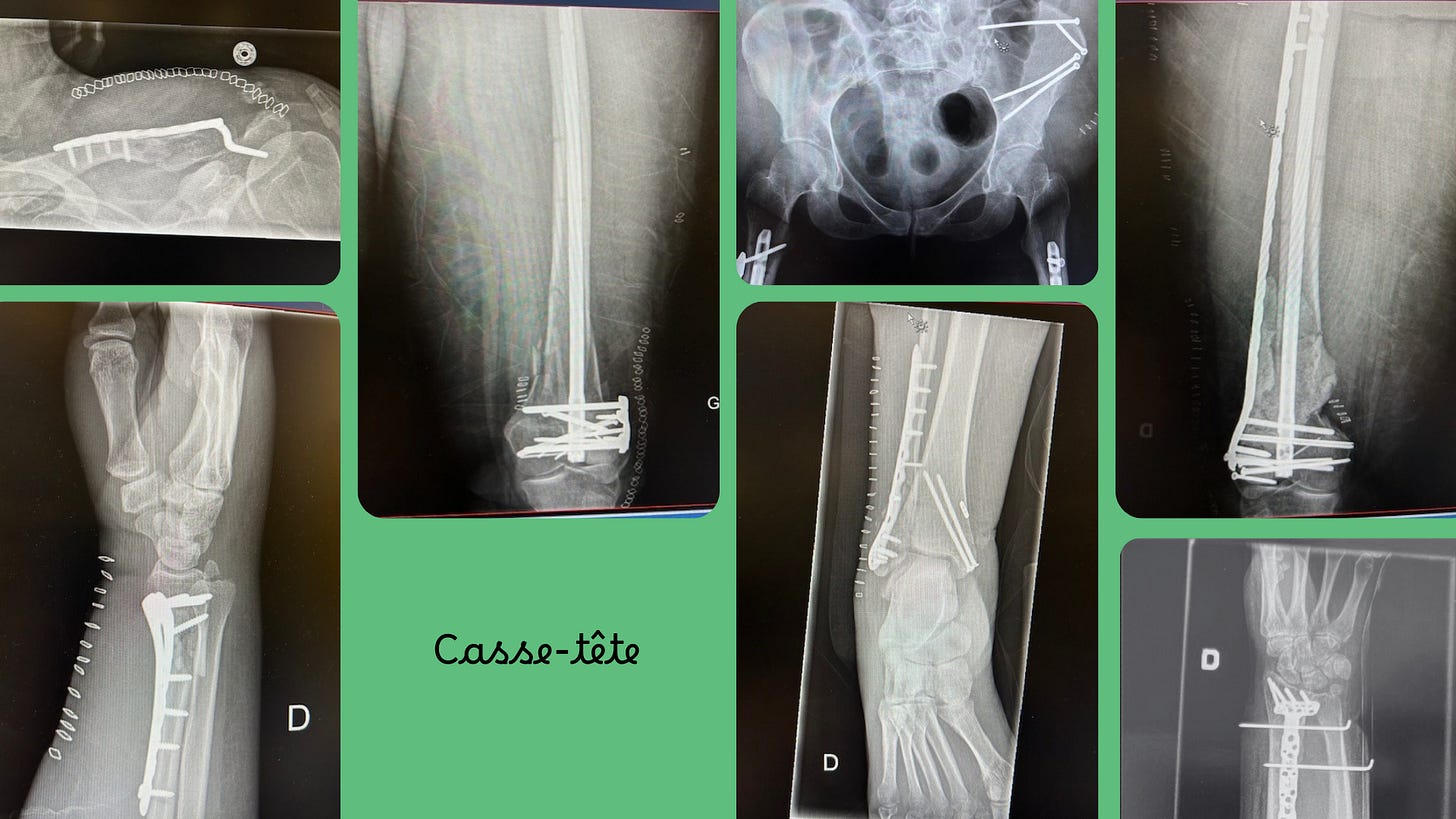

Casse-tête

Bon. J’ai fait exprès de vous flasher mes radiographies. Tout ça, c’est à moi. Je suis propriétaire de l0 livres de métal dans mon corps. Je me doute que je ne passerai pas inaperçue la prochaine fois que je passerai le contrôle-sécurité d’un aéroport. Oups!